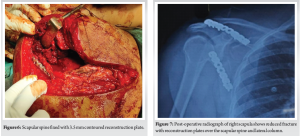

The patient was placed in lateral decubitus position (Fig. 2) and a boomerang incision was taken starting from the inferior angle of the scapula along the medial border of the scapula and then turning over the superomedial angle toward the subcutaneous spine of the scapula. A large skin flap and subcutaneous fat are elevated off the scapular fascia to reveal the supraspinatous, posterior fibers of the deltoid, infraspinatus, teres minor and superior fibers of teres major (Fig. 3). The posterior fibers of the deltoid were released from the spine of scapula and elevated to expose the lateral extent of the infraspinatus and teres minor muscle bellies. A modified Judet approach was taken between the interval between infraspinatus and teres minor to reach the lateral border of the scapula for fracture fixation. The ascending branch of the circumflex scapular artery was encountered and ligated. Care was taken to prevent injury to the suprascapular nerve and vessels as they are in close proximity and are known to be injured during this approach. The lateral column fragments were reduced anatomically and held in place with a reduction forceps (Fig. 4). The scapular body fragment was lateralized due to the pull of the infraspinatus and teres minor. The fragment was medialized toward the glenoid neck fragment and fixed with a 3.5 mm seven-hole precontoured reconstruction plate (Fig. 5). The scapular spine fracture line was exposed by elevating fibres of the supraspinatous from the spine of the scapula and was reduced anatomically with a reduction forceps. The fracture was fixed with a 3.5 mm eight-hole precontoured reconstruction plate (Fig. 6). Copious fluid irrigation was done, and the reflected fibres of the posterior deltoid were reattached to the scapular spine. The interval between infraspinatus and teres minor was not sutured. A drain tube was inserted, which was removed after 24 h. Finally, the Bomerang skin flap was closed in layers, and a sterile dressing was done.

Post-operative radiographs showed excellent fracture reduction (Fig. 7). Post-operative pendulum exercises were started 24 h after surgery, followed by passive range of motion and scapular stabilization exercises at 2 weeks. Active range of motion exercises were started at 6 weeks post-surgery. Once 90% of the normal range of motion was achieved in all plane’s scapular, rotator cuff, and deltoid strengthening exercises were initiated at 4 months post-surgery. The patient shows a good functional outcome (Fig. 8) and radiological union (Fig. 9) at 8 months post-surgery.